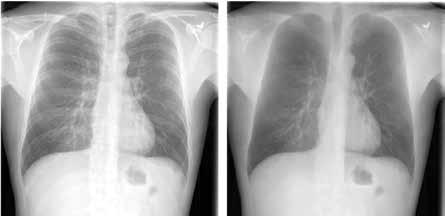

Bone suppression is also popular. This technique removes bones from CXR images to enhance visibility and prevent overlap with disease signs (Figure 2). Researchers have studied bone suppression using different methods, including using image filtering, gradient differences, or separating bone structures from soft tissue using a DCNN model. Bone suppression has been shown to improve the performance of deep models for detecting various diseases, including lung cancer and COVID-19. (Figure 2)